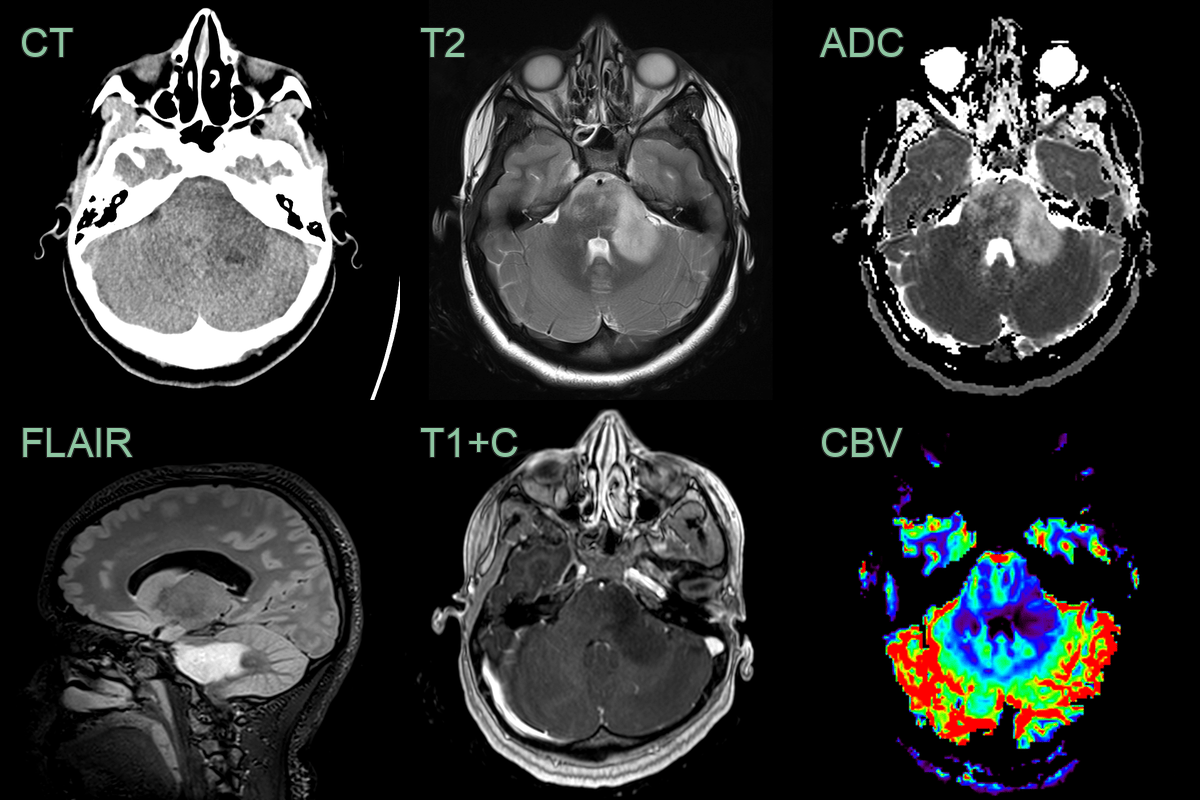

- 20-year-old patient presetned with headaches, blurred vision, nausea and vomitting.

- MRI showed a diffuse T2-hyperintense lesion centred in a mildly expanded cerebellar peduncle.

- Lower ADC values, potentially representing areas of higher celluarity, corresponded to a region of mildly increased rCBV (1.4 relative to the contralateral side).